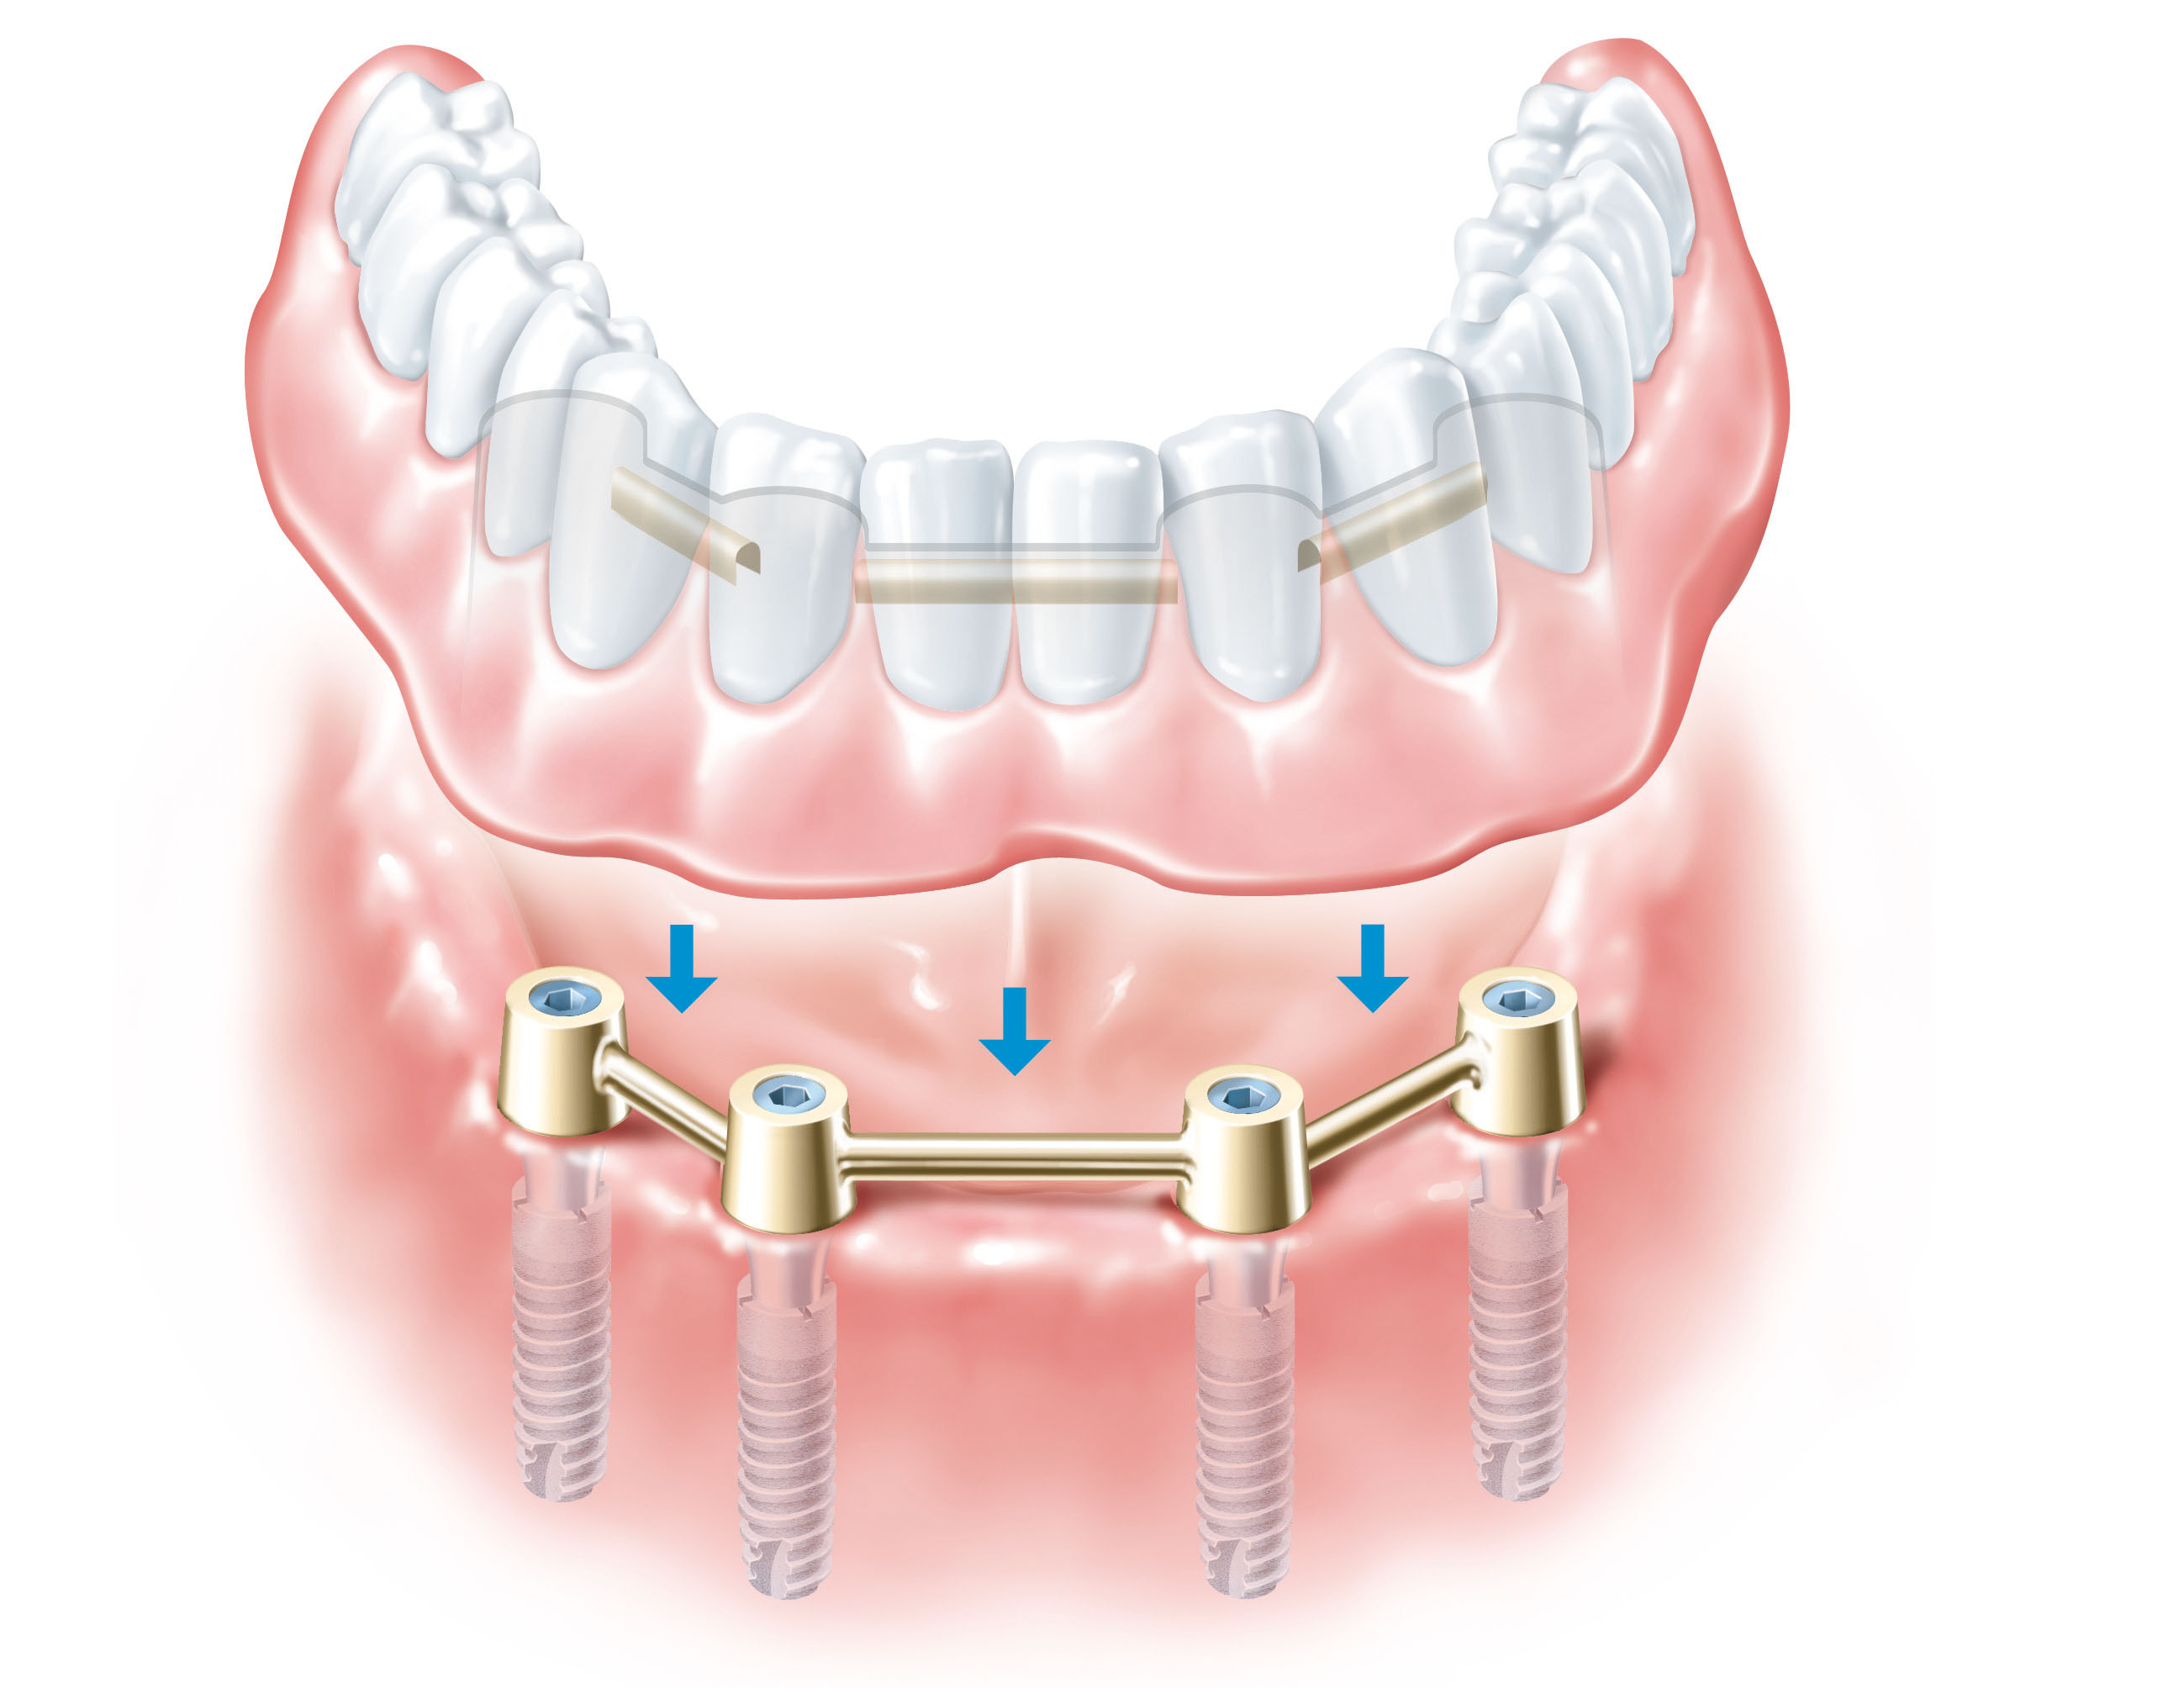

- Балочные конструкции